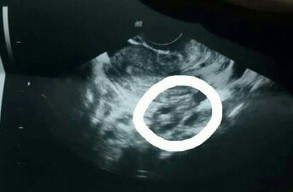

Normal po ba sya sa 7 weeks na pregnant??